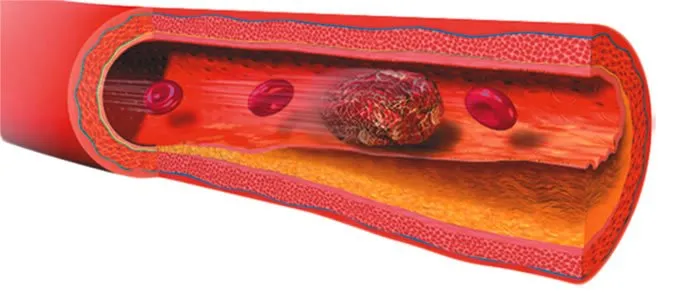

NSAIDs May Raise Risk of Blood Clots Developing in Deep Veins

COX-2 inhibitors are associated with venous thromboembolisms, but experts say use of the painkillers should be looked at on a case-by-case basis.

You may take a pain reliever to help ease discomfort ranging from a mild headache to joint pain related to severe arthritis. But if youre at risk for a blood clot (thrombosis) in a deep vein, you may want to think twice about a particular painkiller: a COX-2 inhibitor (Celebrex).A recent analysis, published in the journal Rheumatology, found that the use of COX-2 inhibitors more than doubles the risk of venous thromboembolism (VTE)-the development of a blood clot in a deep vein that may then travels to the lung and form a pulmonary embolism. The VTE risks werent as significant among people who use COX-1 inhibitors, such as aspirin. COX-1 and COX-2 inhibitors are part of a class of medications known as nonsteroidal, anti-inflammatory drugs (NSAIDs).